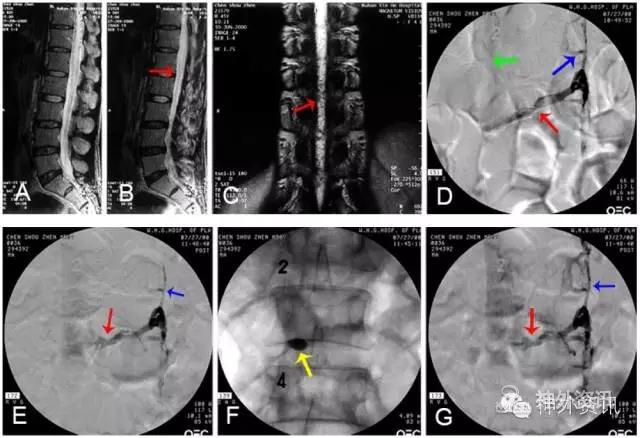

图14: 第三腰横静脉狭窄致脊髓静脉高压综合征A~C. MRI,红色↑示血管流空影;D、E. 第三腰横静脉造影,红色↑示左第三腰横静脉狭窄,绿色↑示向下腔静脉回流少,蓝色↑示向脊髓静脉回流;F. 球囊扩张治疗第三腰横静脉狭窄致脊髓静脉高压综合征,黄色↑示扩张球囊;G. 球囊扩张后,黑色↑示狭窄腰横静脉向下腔静脉回流通畅。